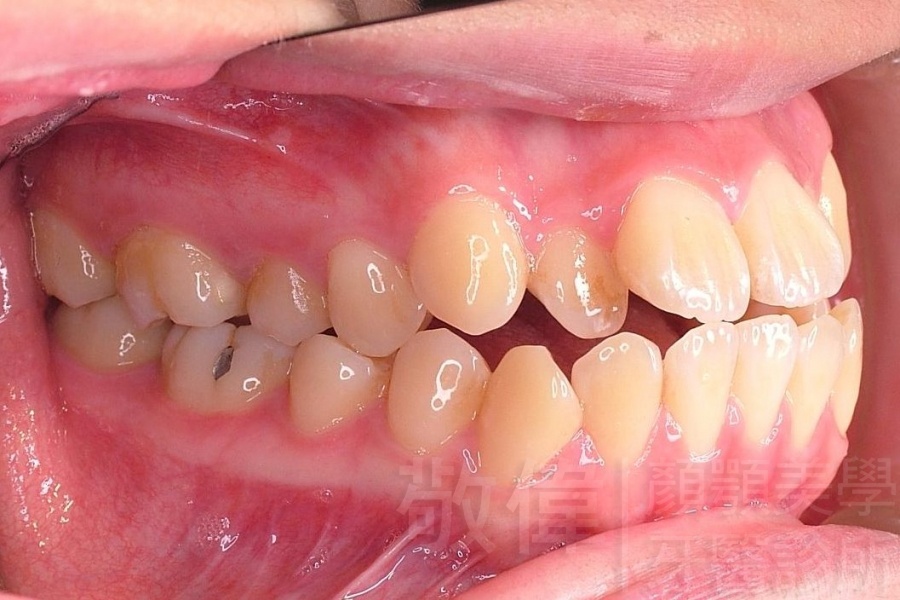

齒顏矯正/戽斗、亂牙、爛牙,變身 免植牙的健牙美女

變臉矯正,原來戽斗妹跟大歪臉變成自信正妹

經由本院3D數影X光影像儀分析、與3D齒顎顏矯正技術,再配合口腔顎面正顎專科醫師施以正顎手術治療,雙方共同合作,使患者臉部外觀有很好的改善,大歪變小歪,產生了天南地北的大改變,她的人生也整個變得不一樣。